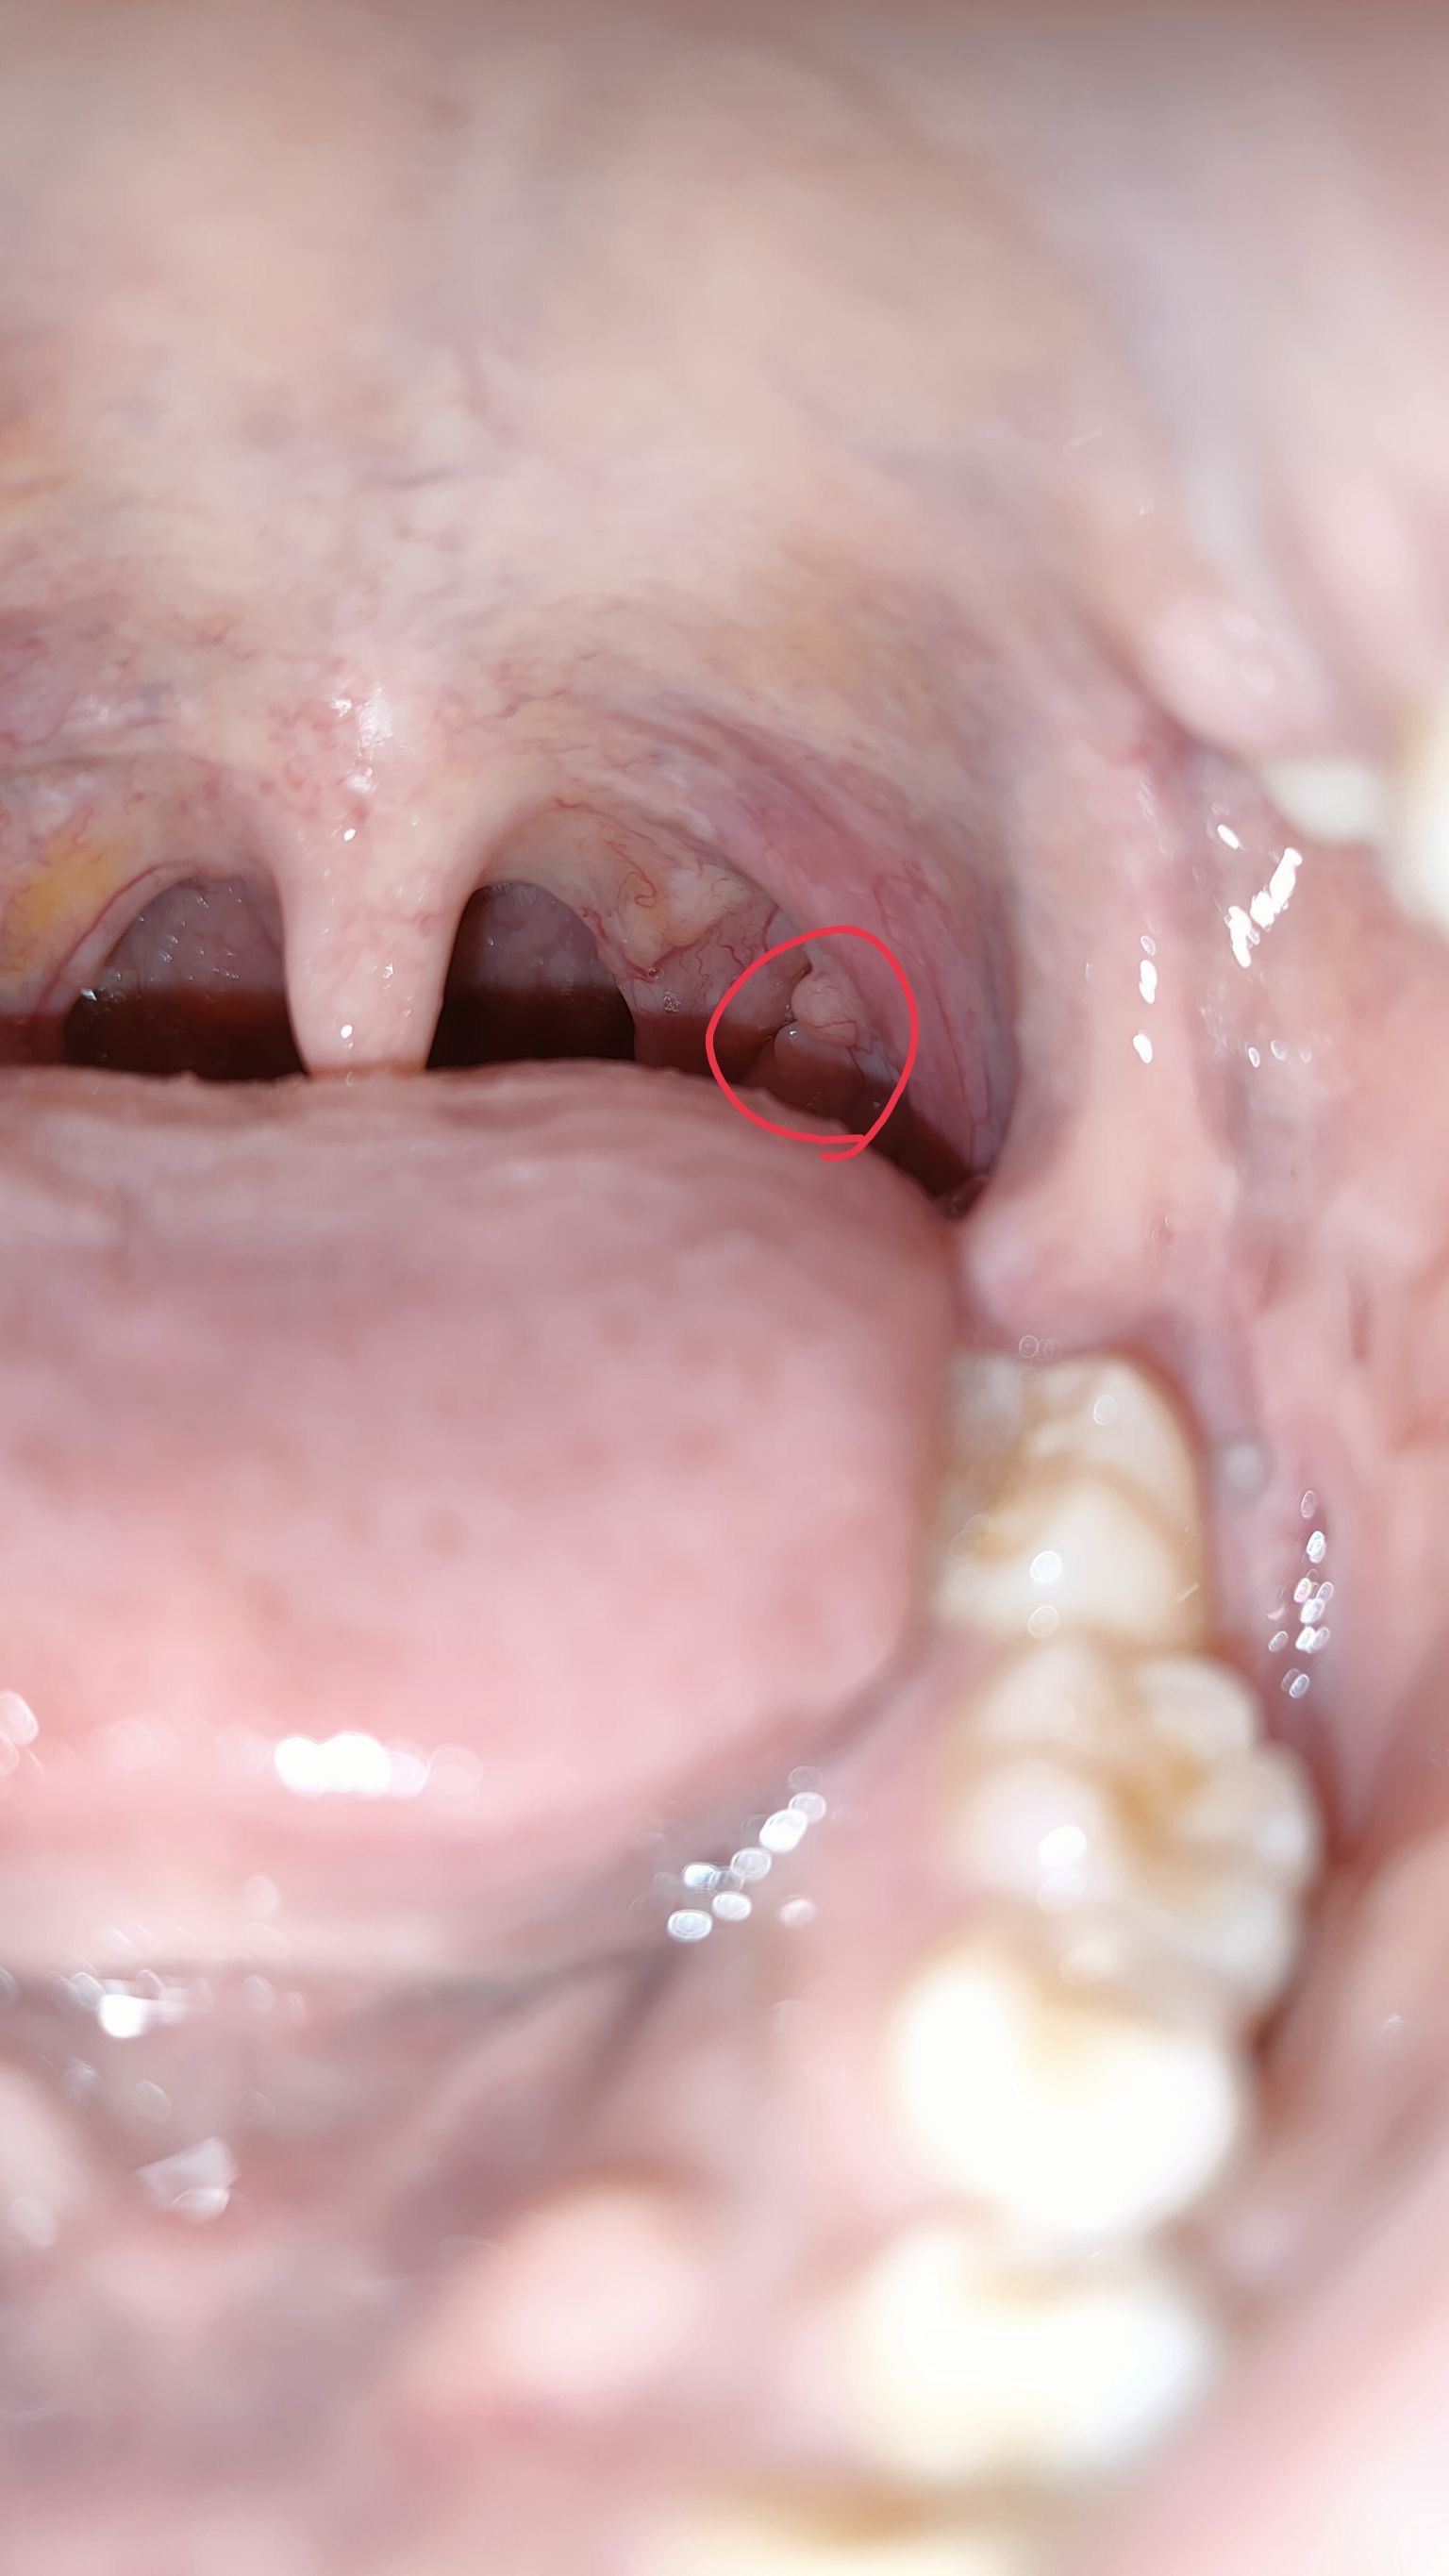

16 พฤษภาคม 2568 12:57:25 #1 https://haamor.com/media/create_topic/20250516125041.jpeg https://haamor.com/media/create_topic/20250516125040.jpeg อันนี้ผมพยายามอ้าให้เห็นสุดๆ แล้วครับ บางครั้งมองผ่านๆ แทบไม่เห็น ไม่เจ็บ ไม่แน่ใจว่าโตหรือป่าวเพราะเพิ่งสังเกตุเลยครับ กลืนอาหารปกติ ผมกังวลเลยอยากให้หมอช่วยดูหน่อยครับ |

19 พฤษภาคม 2568 15:03:38 #2 ติ่งเนื้อปกติครับ พบได้บ่อยๆครับ |